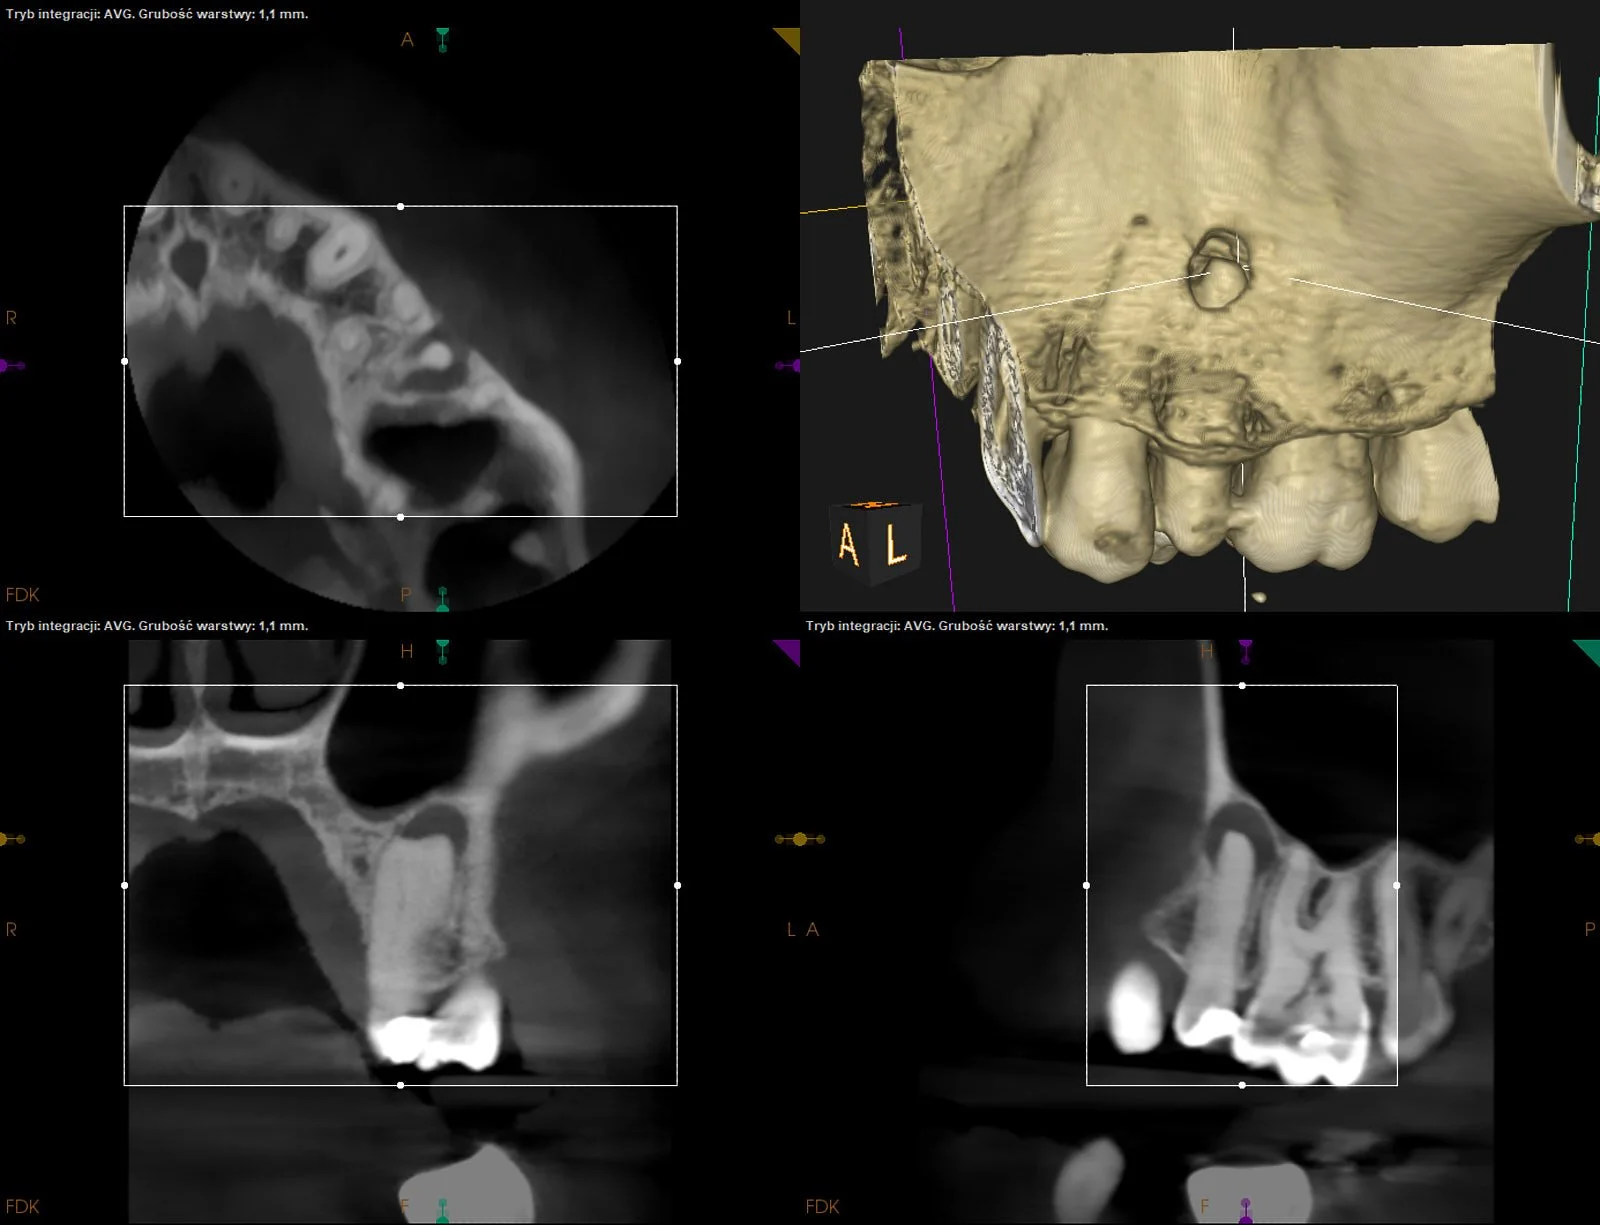

Rozległe zmiany okołowierzchołkowe przy wszystkich siekaczach szczęki po urazie w przeszłości. W następstwie leczeń kanałowych doszło do regeneracji obszaru kości przy wierzchołkach d.12,11 i 22, a d.21 został poddany resekcji wierzchołka korzenia.